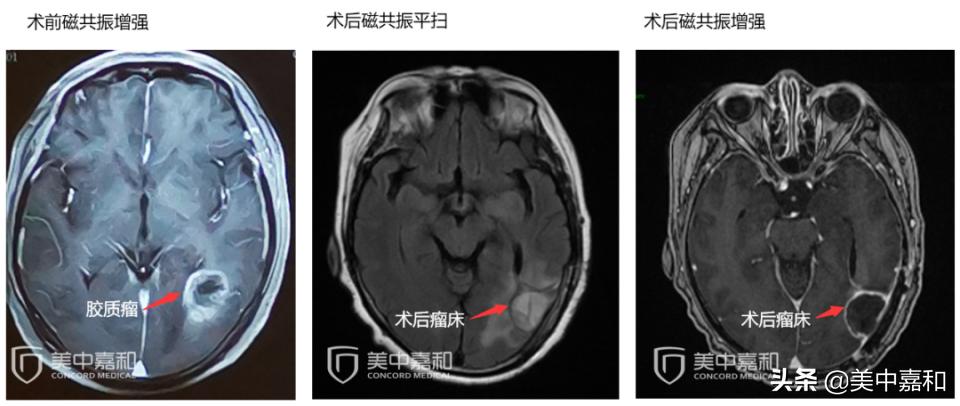

参加此次多学科会诊的吴阿姨,刚退休几年。2020年8月起,时常觉得头晕眼花。2021年1月,到医院检查后,被诊断为胶质母细胞瘤,肿瘤大小为3.3*2.3cm。发现半个月后,即采用手术切除。手术切除后,可以高枕无忧吗?

患者2020年8月起出现头晕不适,逐渐加重,2021.02.02 颅脑MRI增强:左侧侧脑室枕角旁占位,3.3*2.3cm,考虑胶质母细胞瘤可能;右侧侧脑室旁及半卵圆中心亚急性脑梗塞,双侧侧脑室旁多发小缺血灶。

2021.02.19行左颞顶枕深部肿瘤切除手术。术后病理:(左枕)高级别胶质瘤,4*2*2cm,胶质母细胞瘤表型,NOS;WHO IV级,分子报告:GFAP+,Olig2+, Ki67 15%+, P53-, ATRX +/-, IDH1(个别+),CD34(少+),H3K27M(-),H3K27me3(+), Neun(-)。TERTC250野生型,TERTC228C228T 突变型,IDH1R132野生型,IDH2R172野生型;1P无杂合性缺失,19Q无杂合性缺失。2021.03.10颅脑CT平扫:左侧侧脑室枕角旁占位术后改变,术区水肿及引流管影,左枕部颅板下少许积气。胸部CT平扫:右肺尖两枚小结节,左肺下叶小点钙化灶,两下肺少许炎症。